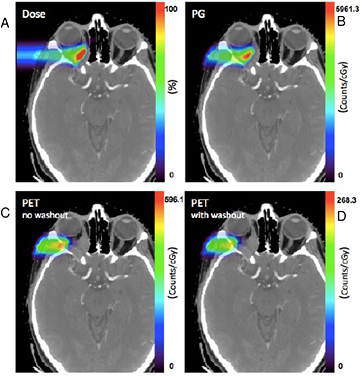

2.5.1. Image guidance: let me see.

CPT is lagging behind in image guidance compared to x-ray therapy, notwithstanding the options offered by particle physics—e.g. detection of prompt γ-rays, secondary charged fragments, or in-beam PET monitoring. In-room imaging by cone-beam computerized tomography (CBCT) or CT-on-rail is now starting to be applied in particle therapy for accurate positioning and daily plan correction. Range uncertainty is the main physics problem of CPT, and beam monitoring and verification must be expanded. Treatments of metastasis or small noncancerous targets will be otherwise always error-prone.

The nuclear fragmentation processes are essential for the calculation of the beam transport and the prediction of their effects. In proton therapy, only target fragmentation occurs resulting predominantly in secondary protons or neutrons. As shown in figure 12, inelastic scattering enhances the lateral spread of the beam. In addition, the creation of slow, densely ionizing recoil nuclei may enhance the biological effectiveness of the beam. In heavy ion therapy, fragmentation severely reduces the fluence of primary ions: in a typical C-ion therapy treatment, only 50% of the ions actually reach the Bragg peak, the others undergoing fragmentation (figure 14). In addition to the lateral spread, these secondaries contribute to the longitudinal spread of the beam (tail in figure 2). Fragmentation can be exploited as a tool for image-guided CPT (see section 5).